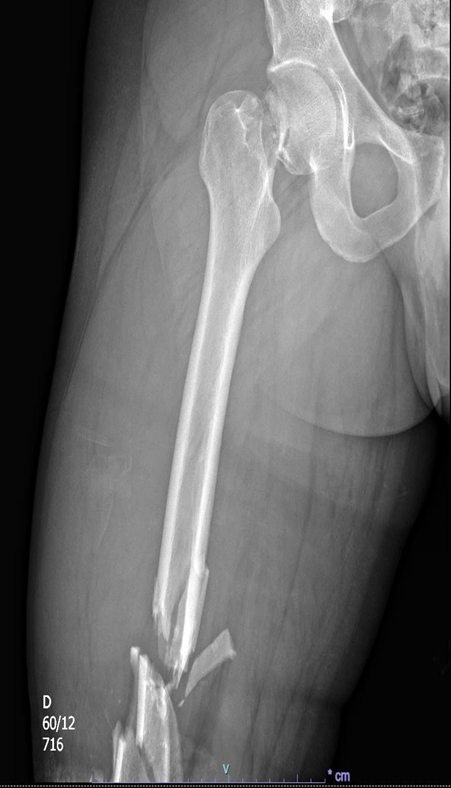

TC abdome e pelve com contraste endovenoso (EV) (02/04/2025): Derrame pleural bilateral – Hemoperitônio disperso na cavidade. Aumento e borramento da adrenal direita, inferindo contusão / laceração. Fígado, pâncreas e adrenal esquerda com situação, dimensões, contornos e coeficientes de atenuação normais. Baço homogêneo. Linha tênue no contorno superior do baço de difícil caracterização devido a artefatos. Ausência de sinais de dilatação das vias biliares intra ou extra-hepáticas. Vesícula biliar normodistendida, paredes finas e conteúdo homogêneo. Rins com topografia, morfologia, dimensões, eixo, contornos e espessura do parênquima normais, não se observando sinais de dilatação dos sistemas coletores. Boa concentração e eliminação do meio de contraste, bilateralmente. Aorta e veia cava inferior com calibre e contornos normais. Ausência de linfonodomegalias retroperitoneais e pélvica. Bexiga repleta, apresentando contornos regulares e conteúdo homogêneo. Próstata com contornos regulares e densidade tomográfica preservada. Trato gastrointestinal de aspecto habitual. Hérnia umbilical, com conteúdo lipomatoso. Fratura cominutiva do colo femoral direito, com desvio.

Figura 5: Tomografia Computadorizada de abdome.

Figura 6: Tomografia Computadorizada de abdome.

TC abdome e pelve com contraste EV (03/04/25): Derrame pleural bilateral, determinando atelectasia passiva. Hematoma adrenal direita medindo 3 cm. Moderado hemoperitônio. Pequeno borramento da gordura perirrenal direita. Fratura em colo femoral direito com desvio. Sem demais alterações agudas do trauma.

Figura 7: Tomografia Computadorizada de abdome.